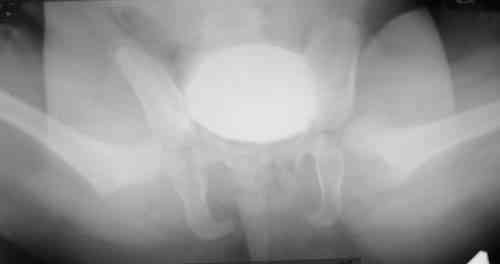

Уважаемые коллеги!Окажите, пожалуйста, консультативную помощь! Девочка, 1 г 9 мДЗ: врожденная патология головного мозга, врожденная дисплазия, подвывих, приводящая контрактура левого тазобедренного сустава, микроцефалия, миоклонические припадки, грубая задержка психофизического развития, с-м Айкарди?

Особенности объективного осмотра в настоящее время:Умеренный тетрапарез. Признаки рахита (деформация костей черепа, четки). Дыхание пуэрильное. Тоны сердца ритмичные, шумов нет. Живот мягкий, безболезненный, печень +1,5 см. Склонность к запорам. Местный статус: резкое приведение левого бедра, относительное укорочение левой нижней конечности. Ограничение отведения в тазобедренных суставах, особенно слева. Гипертонус мышц левой нижней конечности. Ограничение сгибания в левом коленном суставе.

Объем движений (левый ТБС): сгибание-разгибание (фиксированное) 65-165; разведение - D 45, S 65. Положение сустава по отношению к линии Розера-Нелатона - D 0,5 см, S 1,5 см. Хронаксиметрия - возбудимость нервных стволов нижних конечностей в норме, двигательная реакция мышц типичная.

Hi, this is pretty typical windblown hip deformity: abduction on rt side, adduction on the lt(according to your anamnesis kind of CP. Lt side already subluxated , no treatment will lead to further dislocation.I think that best way for treatmen now is : adductor tenotomy on the lt + spica cast ( 50-60 degrees abduction with wood bar between legs), after 6 weeks change to another 6 weeks; than for 6 months night plastic abduction brace.